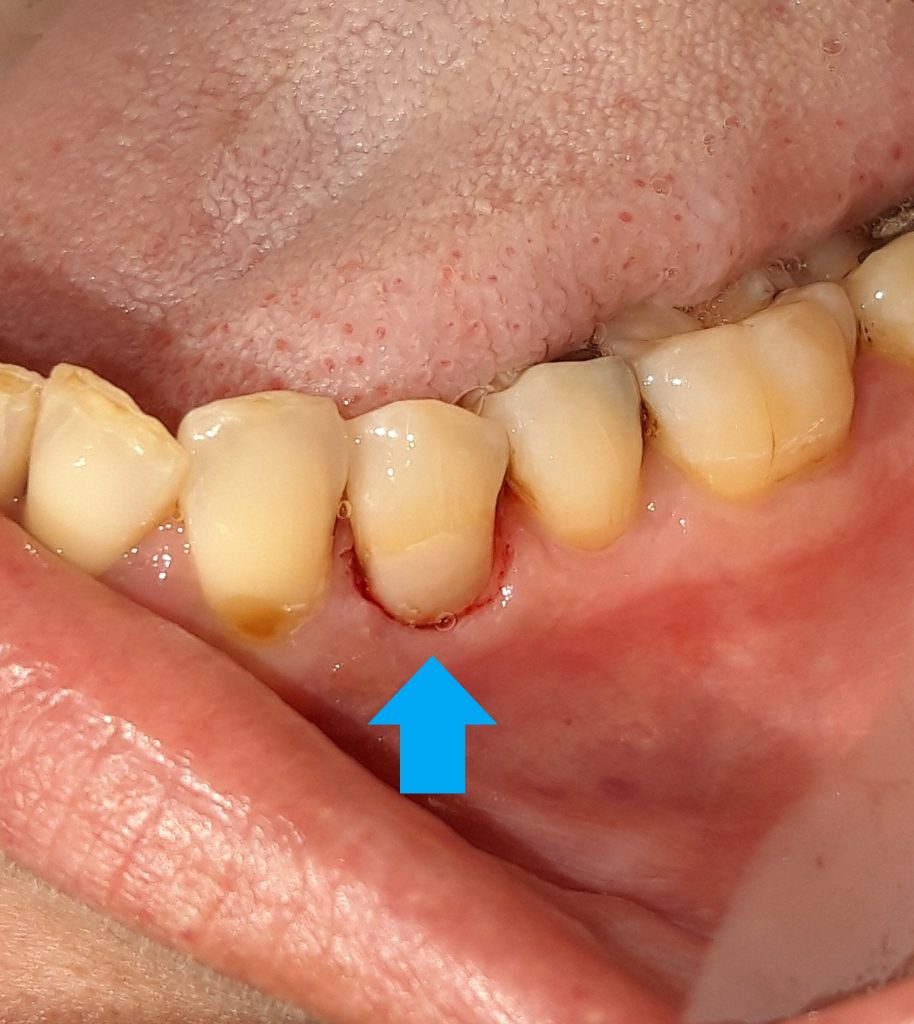

Η τερηδόνα προσβάλλει συνήθως τη μασητική επιφάνεια ενός δοντιού. Σε άλλες πάλι περιπτώσεις είναι δυνατόν να εμφανιστεί στον αυχένα δοντιού. Αρχικά εμφανίζεται σαν μία μικρή καφέ κηλίδα. Εφόσον ο ασθενής δεν επισκεφτεί άμεσα τον οδοντίατρο, είναι δυνατόν η τερηδόνα από τον αυχένα του δοντιού να προχωρήσει σε μεγαλύτερο βάθος και να φτάσει να προσβάλλει το νεύρο του δοντιού. Για το λόγο αυτό είναι σημαντικό ο ασθενής στην εμφάνιση μιας μικρής τρύπας / τερηδόνας να απευθύνεται άμεσα στον οδοντίατρο για την επίλυση οποιουδήποτε οδοντικού προβλήματος προκύπτει. Άλλωστε μία μικρή τερηδονική αλλοίωση αντιμετωπίζεται ευκολότερα και γρηγορότερα συγκριτικά με ένα δόντι που χρειάζεται απονεύρωση.

Στις περισσότερες περιπτώσεις μία τερηδόνα που εμφανίζεται στον αυχένα του δοντιού αποκαθίσταται με λευκό σφράγισμα δοντιού. Πρόκειται για μία απλή και καθόλου επίπονη διαδικασία.